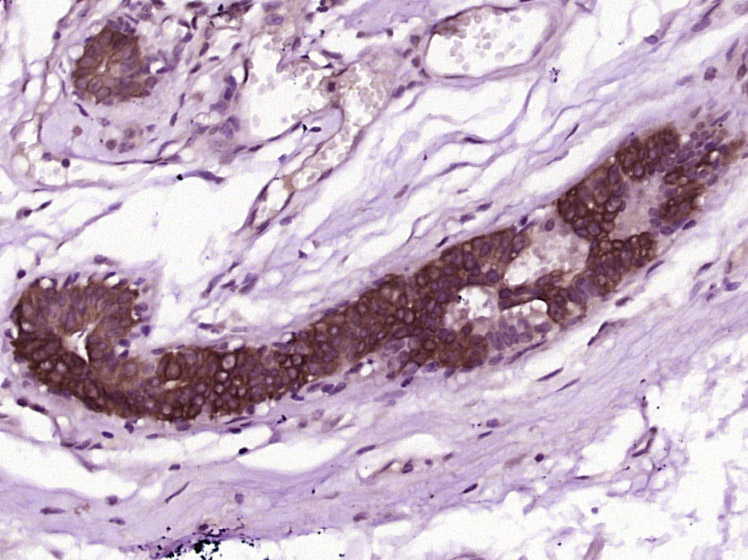

| 英文名称 | CWH43 Rabbit pAb |

| 中文名称 | 细胞壁合成蛋白43抗体 |

| 产品应用 | WB=1:500-2000, IHC-P=1:100-500, IHC-F=1:100-500, IF=1:100-500 Not yet tested in other applications. |

| 交叉反应 | Human (Mouse, Rat, Chicken, Dog, Pig, Cow, Horse, Rabbit, Sheep) |

| {IHC-P} | {1:100-500} |

| {IHC-F} | {1:100-500} |